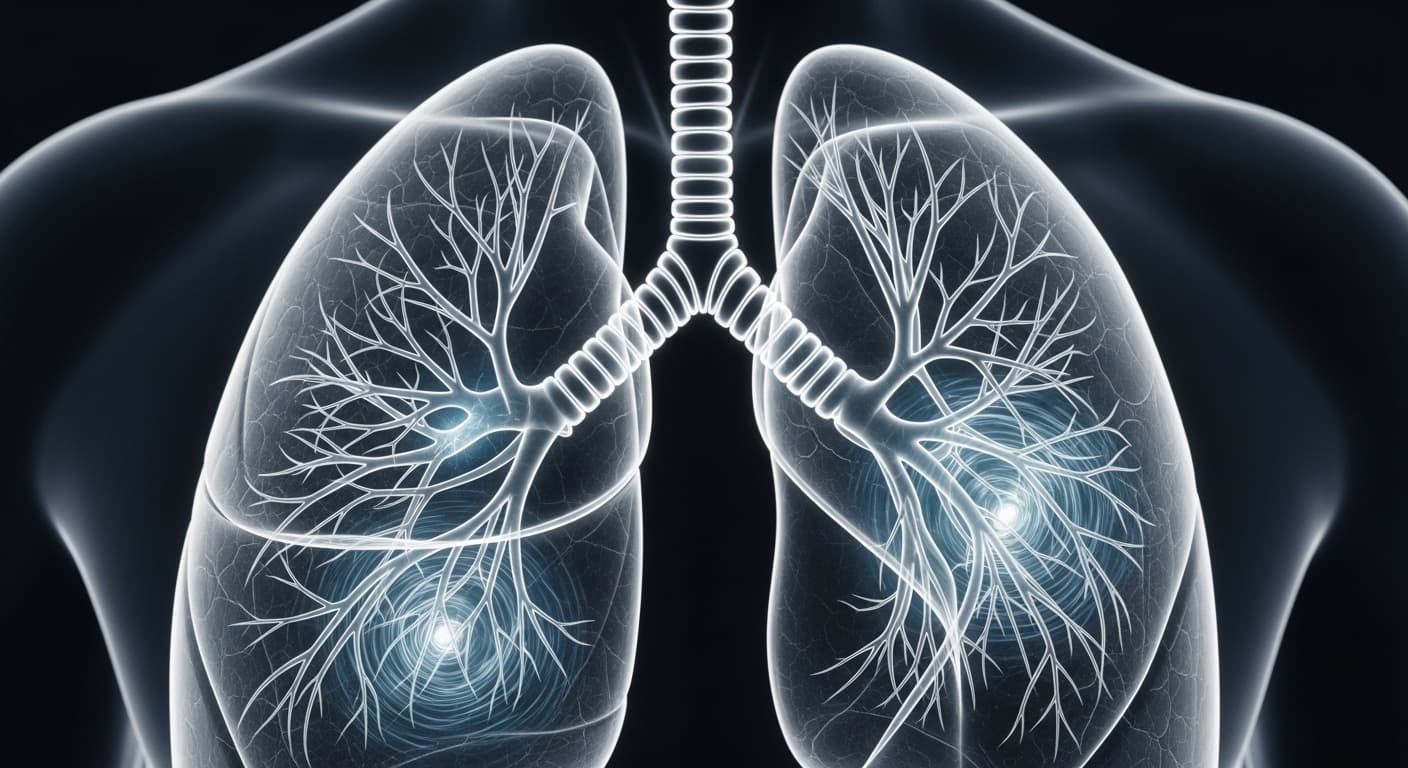

감기는 바이러스 감염으로 인한 급성 호흡기 질환이지만, 바이러스는 우리 몸에서 사라져도 그 흔적은 오래도록 남을 수 있어요. 바로 '만성 기침'이라는 형태로 말이죠. 현대 의학에서는 감기 후 한 달 이상 지속되는 기침을 '만성 기침'으로 분류하는데, 이는 동의보감에서 말하는 '폐에 병이 든 것'과 맥락을 같이 합니다. 감기 바이러스가 폐와 기관지를 침범하면, 우리 몸은 염증 반응을 일으켜 바이러스와 싸워요. 이 과정에서 기관지 점막이 손상되고 과민해지는데, 바이러스가 사라진 후에도 염증 반응이 완전히 가라앉지 않거나, 손상된 점막이 완전히 회복되지 않으면 기관지가 계속 자극에 예민하게 반응하게 됩니다. 이를 '기관지 과민성'이라고 하는데, 먼지, 찬 공기, 매연, 건조한 공기 등 사소한 자극에도 기침 반사가 쉽게 유발되는 상태를 말해요. 더 나아가, 만성 기침은 단순히 기관지의 문제만을 넘어설 수 있어요. 바이러스 감염은 우리 몸의 신경계에도 영향을 미칠 수 있답니다. 특히 미주신경(Vagus nerve)은 폐와 기관지를 포함한 다양한 내장 기관의 감각과 운동을 조절하는데, 감염 후 미주신경이 과도하게 활성화되거나 민감해지면 기침 반사 회로가 지속적으로 자극될 수 있어요. 뇌의 기침 중추는 평소보다 작은 자극에도 '기침!'이라는 명령을 내리게 되는 거죠. 또한, 위식도 역류 질환(GERD)이나 후비루 증후군(Upper Airway Cough Syndrome, UACS)도 만성 기침의 흔한 원인입니다. 위산이 역류하여 식도를 자극하거나, 콧물이나 분비물이 목뒤로 넘어가는 것이 기침을 유발하는 거죠. 동의보감에서 '담음'이 폐를 막는다고 표현했던 것처럼, 현대 의학에서도 과도한 점액 분비나 위산 역류가 기관지를 자극하여 기침을 일으킨다고 봅니다. 이는 단순히 폐 자체의 문제뿐만 아니라, 소화기계나 상기도의 불균형이 전신적인 호흡기 증상으로 나타날 수 있음을 시사해요. 더욱 중요한 것은, 이러한 만성 기침이 심리적인 스트레스와 상호작용한다는 점입니다. 기침 때문에 잠을 못 자거나 일상생활에 지장을 받으면 스트레스 호르몬인 코르티솔 수치가 높아지고, 이는 면역 기능을 저하시켜 염증 반응을 악화시키고 기관지 과민성을 더욱 심화시킬 수 있어요. 신경내분비계의 불균형이 만성 기침의 고리를 더욱 단단하게 만드는 셈이죠. 따라서 만성 기침은 단순히 폐만의 문제가 아니라, 우리 몸의 면역계, 신경계, 소화기계, 심지어 정신적인 상태까지 아우르는 복합적인 접근이 필요한 질환이랍니다.